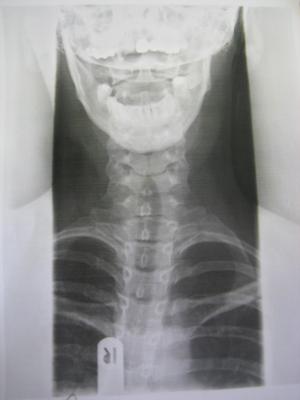

Heute war ich hier beim Durchgangsarzt,da momentan alle Orthopäden hier Urlaub haben bis nach Ostern und ich Probleme habe meinen Kopf vernünftig zu bewegen.Er hat Röntgenbilder gemacht und ich hab einen richtigen Schock bekommen.Das was ich vermutet habe,hat sich wohl bestätigt,es ist schlimmer geworden mit der Skoliose und ich muss sofort zu einem Orthopäden.Ich habe stärkere Schmerzmittel bekommen und mein Arzt meint,ich brauche wohl ein Korsett.....

Ich hab mal die Bilder vom Röntgen angehängt.Den Grad der Verkrümmung weiss ich leider noch nicht.Aber kann mir vielleicht jemand was zu den Bildern sagen?